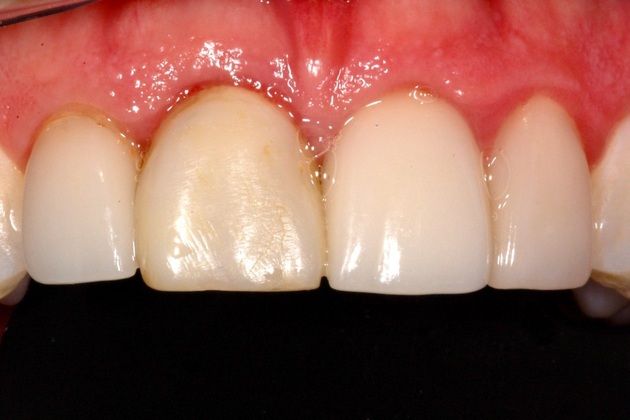

Internal or external resorption of roots is an idiopathic condition affecting teeth in traumatic occlusion. It is a "silent killer" of teeth. We recently completed a case where one tooth had to be replaced with a dental implant and the other required a new dental crown following the exploration of its root for evidence of internal resorption. The Nobel Biocare implant system was used and the patient never went without a tooth. Immediate temporization during the surgery to remove the root was deployed and the patient was not inconvenienced by a removable temporary solution.